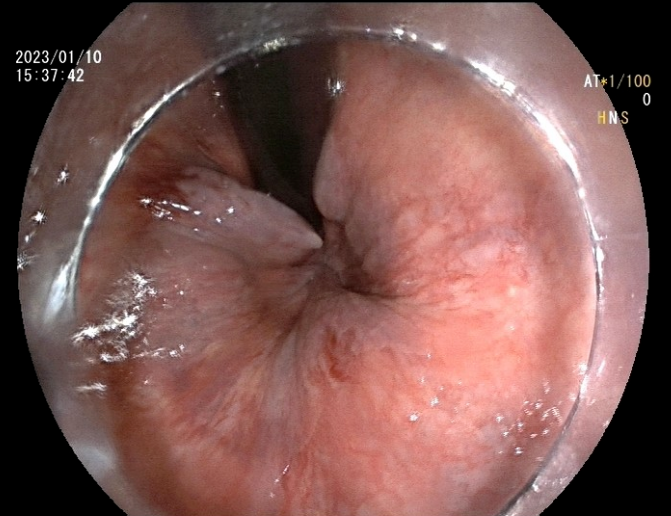

近日,北京燕化医院消化内科再次完成一例内镜下内痔硬化剂注射术,成功为患者解决长期便血的困扰。

患者李某,男,48岁,主因间断便血2月余,加重20天入院。既往高血压病1级(低危)、高脂血症。患者饱受2个多月间断鲜血便的困扰,且便后伴有异物脱出,门诊以“II期内痔伴出血”收入消化内科。消化内科副主任王铁汉查房时,根据患者目前状况及手术耐受情况,建议其行内镜下内痔硬化剂注射术,并与患者讲解了此术式的优点及相关事项,经过衡量再三,患者同意实施内镜下治疗。

入院的第三天,张芙蓉主治医师在王铁汉副主任的指导下,为患者实施内镜下内痔硬化剂注射术,仅数分钟,手术成功完成。术后患者无任何不适症状,并于三日后出院,术后第7、15天随访,患者表述术后未感觉到任何不适,困扰多月的血便问题得以完美解决。